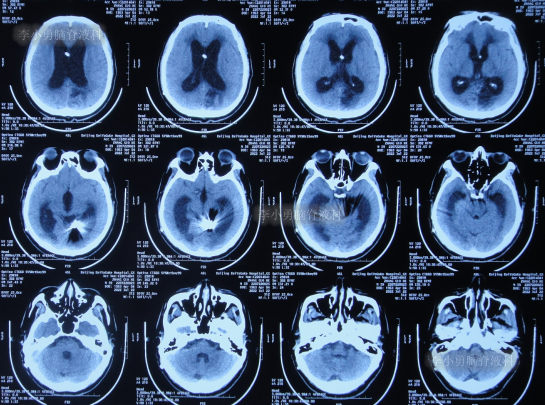

2022年3月23日(脑动脉瘤栓塞术后5天),查头颅CT示积血减少(图-3);术后身体恢复良好,能自行下地活动。

图-3:2022年3月23日头颅CT